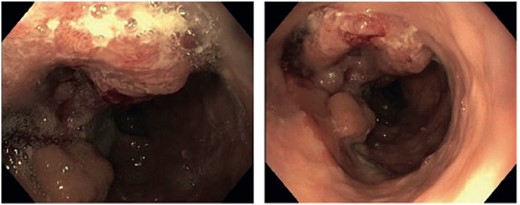

We report the case of a 57-year-old patient who presented to our institution with histologically confirmed colorectal adenocarcinoma of the interposed colon after esophagectomy in infancy. At the age of 6 months, the patient underwent surgery for esophageal atresia with resection and colonic interposition. At the age of 4 years, a segment of the interposed colon was resected, most likely due to kinking. No records on these operations performed at a renowned institution in Germany around 1965 exist anymore. In December 2021, the patient presented with hematin reflux via an inserted gastric tube and underwent esophago-gastro-duodenoscopy, while he was hospitalized for myocardial infarction. A hemorrhage in the area of the intestinal interposition was clipped, but there were abnormalities of the mucosa of unclear dignity, which is why a upper endoscopy was repeated after discharge. The examination in August 2022 revealed a mass 23 cm from the incisors, occupying about one-third of the circumference (Fig. 1). The histological workup of the samples taken showed colonic mucosa including a colorectal adenocarcinoma. Staging CT scans of the thorax and abdomen revealed marked wall thickening of the neoesophagus proximal to the tracheal bifurcation over ~7.5 cm (Fig. 2). There was no evidence of suspicious pulmonary or hepatic lesions. Thus, the patient was planned for primary surgical resection, in accordance with the standard approach for colon cancer, after discussion in our multidisciplinary team meeting. The patient underwent thoracoabdominal esophagectomy with resection of the colonic interposition en bloc with adjacent healthy esophagus orally and distally. Reconstruction was performed by gastric pull-up. Due to the previous surgery, marked adhesions in the thorax were encountered and lead to an intraoperative injury of the lung, resulting in an atypical lung resection of the right upper lobe. Histological examination of the surgical specimen revealed moderately differentiated colorectal adenocarcinoma with lymphogenous metastasis (G2, pT3, pN2a (4/13), L0, V0, Pn0, R0, cM0). Approximately 2 months after surgery, adjuvant chemotherapy with CAPOX (capecitabine and oxaliplatin) was started.

Endoscopic view showing a tumor of the transposed colon 23 cm from the incisors.